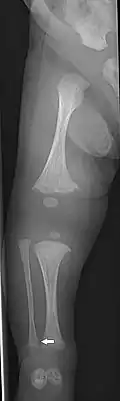

OI Type V in an adult

Type V

Having the same clinical features as Type IV, it is distinguished histologically by "mesh-like" bone appearance. Further characterized by the "V triad" consisting of (a) radio-opaque band adjacent to growth plates, (b) hypertrophic calluses at fracture sites, and (c) calcification of the radio-ulnar interosseous membrane.[24]

OI Type V leads to calcification of the membrane between the two forearm bones, making it difficult to turn the wrist. Another symptom is abnormally large amounts of repair tissue (hyperplasic callus) at the site of fractures. Other features of this condition include radial head dislocation, long bone bowing, and mixed hearing loss.